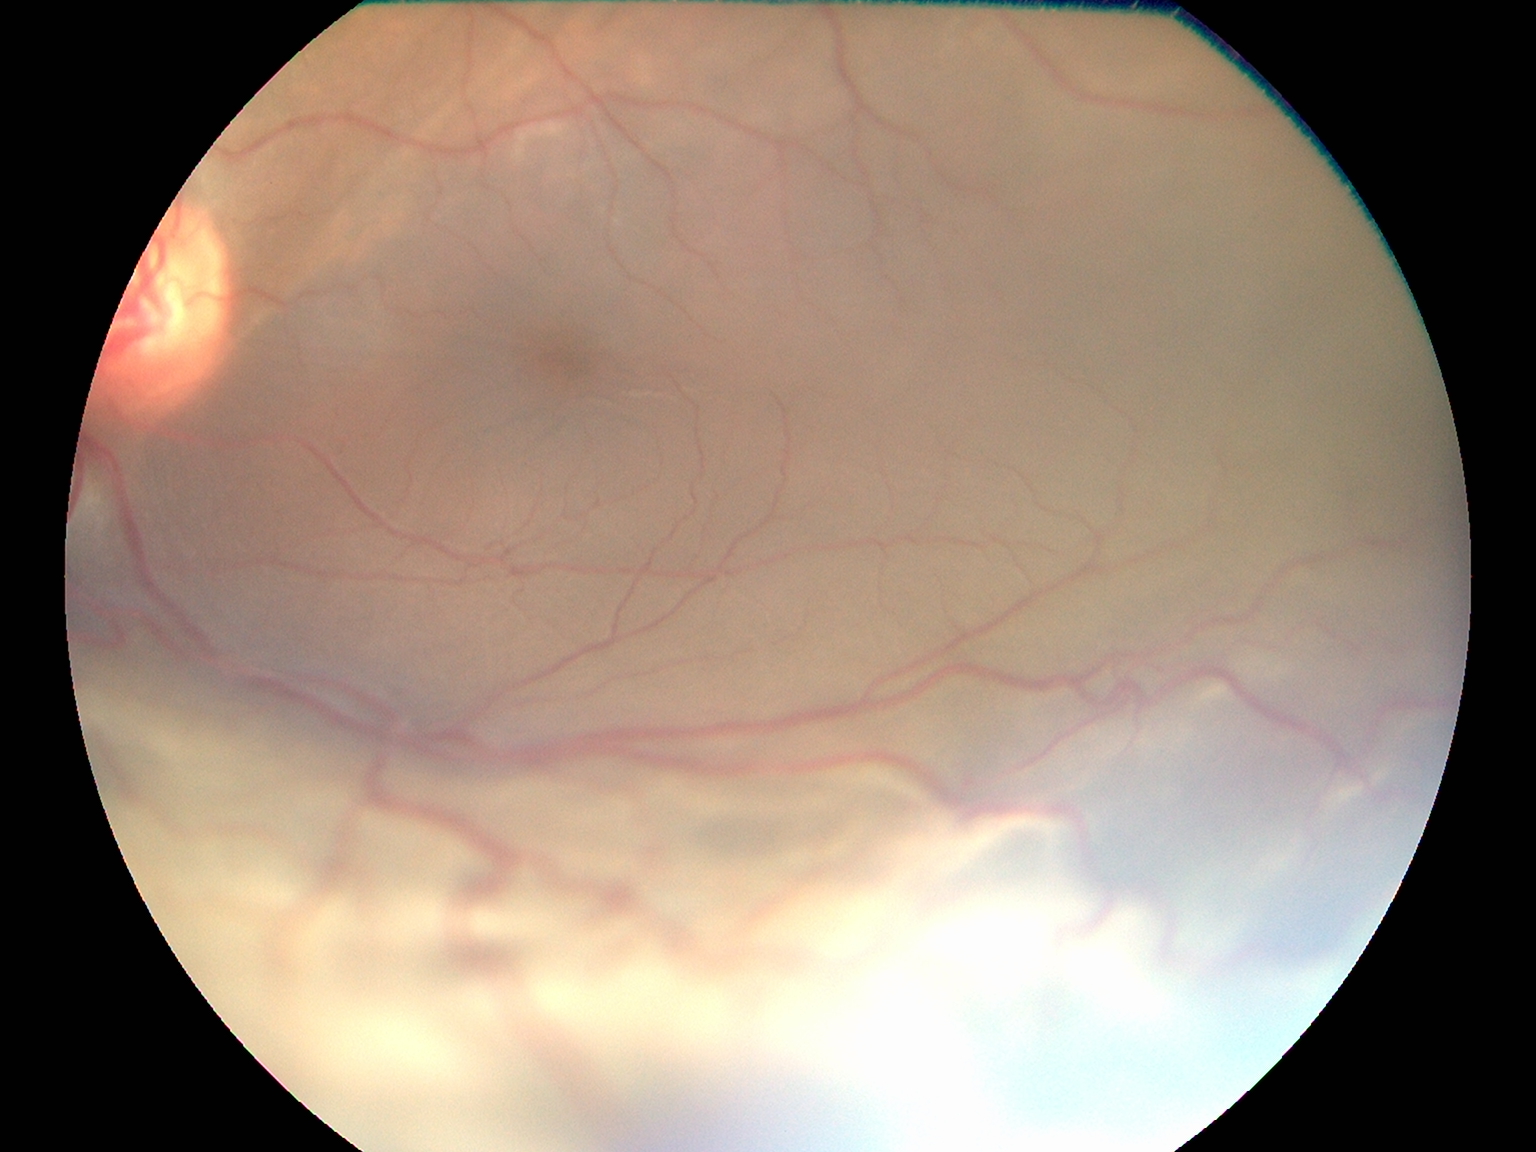

Top Retina Specialist

Advanced Retina Treatment